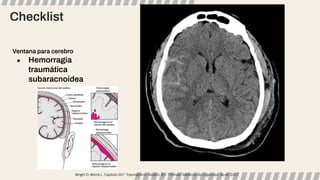

Ventana para cerebro

● Hemorragia

traumática

subaracnoidea